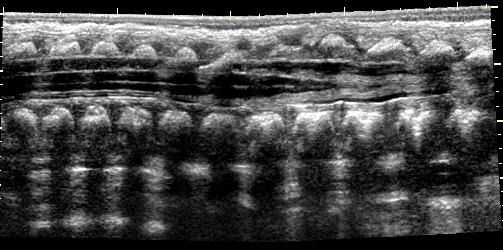

Malrotation-volvulus. During the normal development of the intestinal tract, the intestinal loops make three 90 degree clock-wise rotations around the mesenteric superior artery (MSA.) If this rotation only partially occurs during the embryonic development the intestines remain in a non-rotational or malrotational position, the mesenteric root will be shorter and the cecum will be weakly attached. This anatomic positioning can be symptom free throughout a lifetime, but it predisposes for volvulus. Volvulus can occur at any age, but it is most frequent in the first months of life, when it abruptly occurs with acute bilious vomiting. In this state the intestines around the mesenteric root twist, end up in a complete obstruction that can lead to a rapid death of the intestines. Ultrasonography can depict the mesenteric superior vein (MSV) coiled up around the MSA, so called “whirlpool”-sign.

14. “Whirlpool” sign The mesentery and the superior mesenteric vein, as it coils around the superior mesenteric artery. Volvulus. US exam.